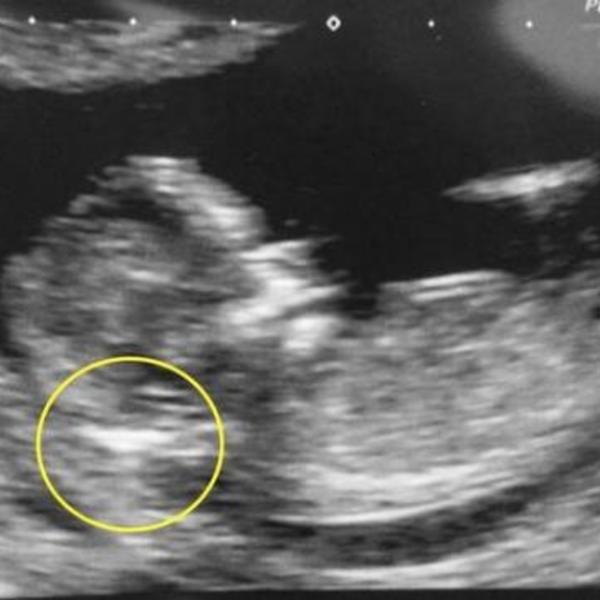

Fredi, dečak koji ima Daunov sindrom, bori se s leukemijom i na svoj treći rođendan.

Do sada je prošao četiri hemoterapije, a ispred njega je dug put oporavka. Očekuje se da će se još 2 godine boriti s bolešću.